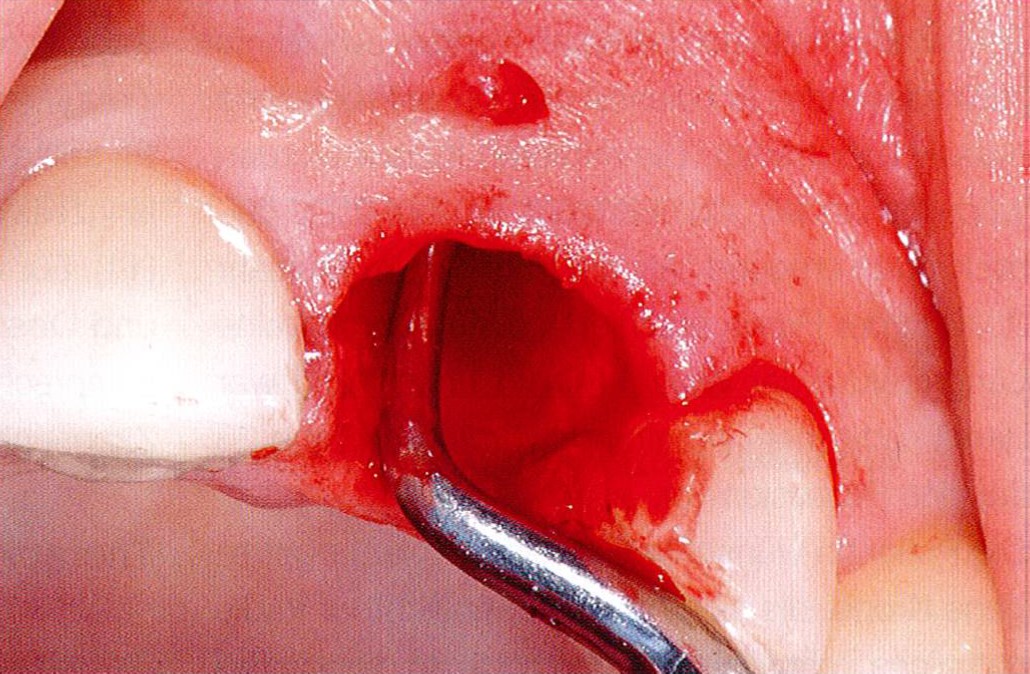

2/18 - Obvious loss of the buccal lamellaGBR together with soft tissue augmentation with mucoderm® and maxresorb® - Dr. S. Scherg

3/18 - Clinical situation 6-8 weeks after extraction, vestibular viewGBR together with soft tissue augmentation with mucoderm® and maxresorb® - Dr. S. Scherg